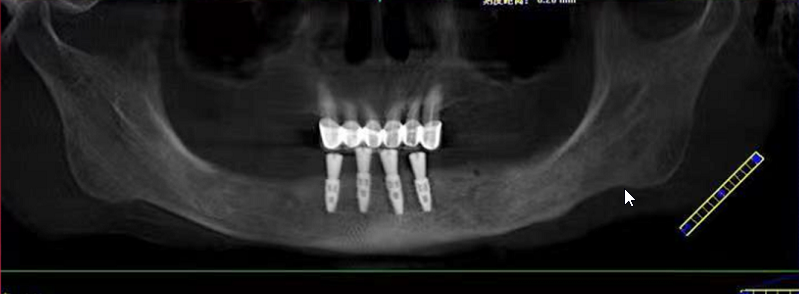

赖女士种牙前CT

今天活动上有一位这样特殊的分享嘉宾——赖女士,今年69岁,需要种植的是下半口。赖女士为了想种好牙辗转了好几家医院,因为她的右边牙龈和舌头是连在一起的,去过其它医院说要割开才能种牙,后来打听到麦芽口腔姚院长临床经验丰富,过来看诊后,给出的主案可以用数字化导板进行种植牙,并不用割开原本连在一起的牙龈和舌头,赖女士听到此方案相当满意。